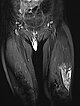

In coronal, T2-weighted, fat-suppressed MRI at 32 months of age, the characteristic strongly hyperintense (= white) signal of a slow-flow vascular malformation is found in the labial lesion. In addition, a similarly strong hyperintense signal in an intramuscular lesion is seen in the vastus lateralis muscle of the left thigh. Thus, a vascular malformation is very likely.